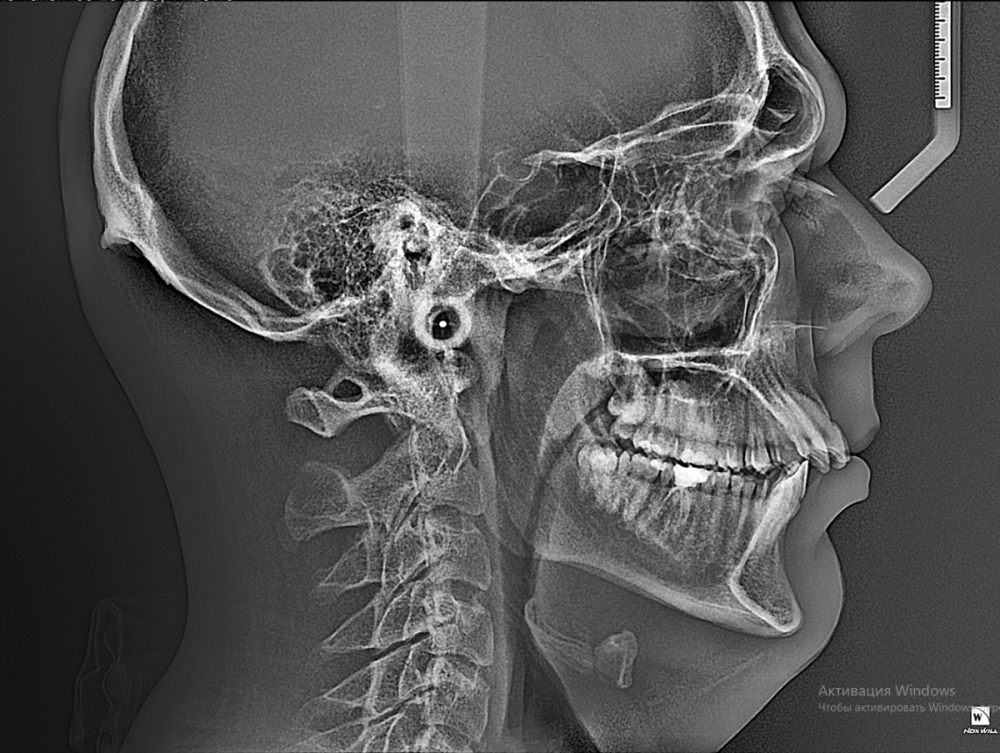

Dmitry002442 Опубликовано 21 июля, 2023 Поделиться Опубликовано 21 июля, 2023 (изменено) У ортодонта еще не был, хотел сначала тут поинтересоваться. Сделал снимки и получил следующее: сагиттальная щель 10,5 мм, параметр Wits 7,6 мм и прочее. Дистальный и открытый прикус. Хотел узнать необхо дима ли в таком случае члх или можно обойтись только брекетами? Изменено 21 июля, 2023 пользователем Dmitry002442 Ссылка на комментарий

АнтонТЛТ Опубликовано 21 июля, 2023 Поделиться Опубликовано 21 июля, 2023 Трг с расчетами и оптг это конечно хорошо, но нужны фото моделей челюстей или внутриротовые сканы. Думаю тут всё обойдется без члх, но возможно внутрикостные опоры нужны будут. 1 Ссылка на комментарий